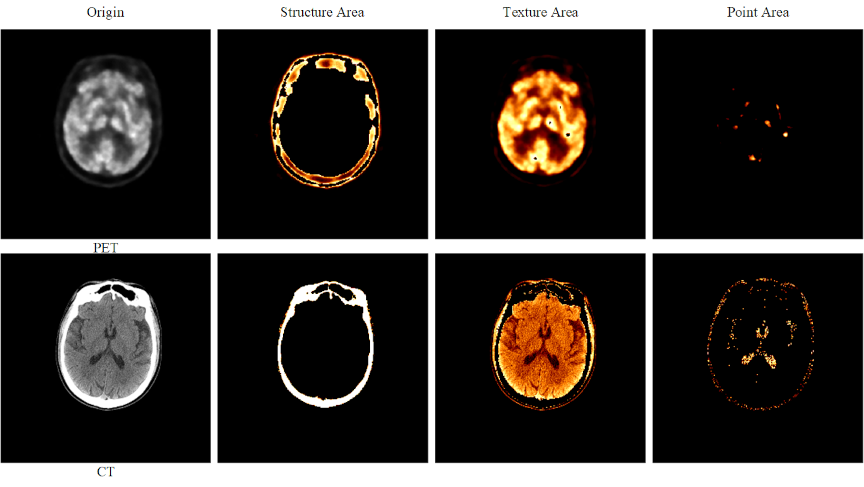

Fig. 5. Brightness-sensitive loss components. The first row displays PET images, whereas the second row presents CT images. From left to right, the four columns show: (1) the original image, (2) the image after applying a structural threshold (Structure Area), (3) the image after applying a texture threshold (Texture Area), and (4) the image after applying a detailed region threshold (Point Area).

To incorporate pixel-brightness characteristics, we propose a brightness-sensitive loss (BSLoss), which assigns weights to structural, textural, and point-like regions based on intensity (Fig. 5). First, the predicted image \(\mathbf{\hat{y}}\) and ground truth \(\mathbf{y}\) are mapped from \([-1,1]\) to \([0,1]\):

Fig. 12. Region segmentation in complete PET–CT images using the brightness-sensitive loss function. In the first row, Columns 1–3 show the segmented regions, and the last column shows the complete PET image. The second row shows Columns 1–3 display its segmented regions, and the complete CT image in the last column.

Model Interpretability: This study employed a streamlined encoder–decoder architecture. Multistage cascade experiments of up to four stages revealed that the three-stage variant achieved the best overall performance. Building upon this observation, we introduced a brightness-sensitive loss function that decomposes the cross-modal translation task into three brightness-weighted subtasks, enabling each generator to focus on a specific high-priority region, as illustrated in Fig. 12.

The first row of Fig. 12 presents the original PET image and its three segmented regions obtained via thresholding within the brightness-sensitive loss. The second row shows the corresponding original CT image and its segmented regions. Conceptually, this design parallels partitioning a style-transfer problem into three brightness-defined regions, processed sequentially by three generators, each dedicated to a distinct focus area. The synergistic integration of the brightness-sensitive loss with the multistage generator not only improves quantitative accuracy but also substantially enhances the interpretability of the entire framework.